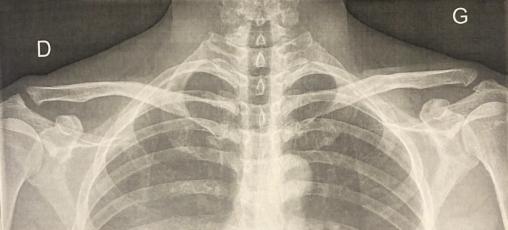

L’examen clinique met en évidence une touche de piano (fig. 1) douloureuse à la palpation et un élargissement visible de l’articulation acromioclaviculaire, sans limitation des amplitudes articulaires.

L’examen clinique révèle une articulation tuméfiée (fig. 1), une douleur à la palpation et à la manœuvre du cross arm (ou test d’adduction forcée). Selon le degré d’ostéolyse, la mobilité de l’épaule peut être limitée.4